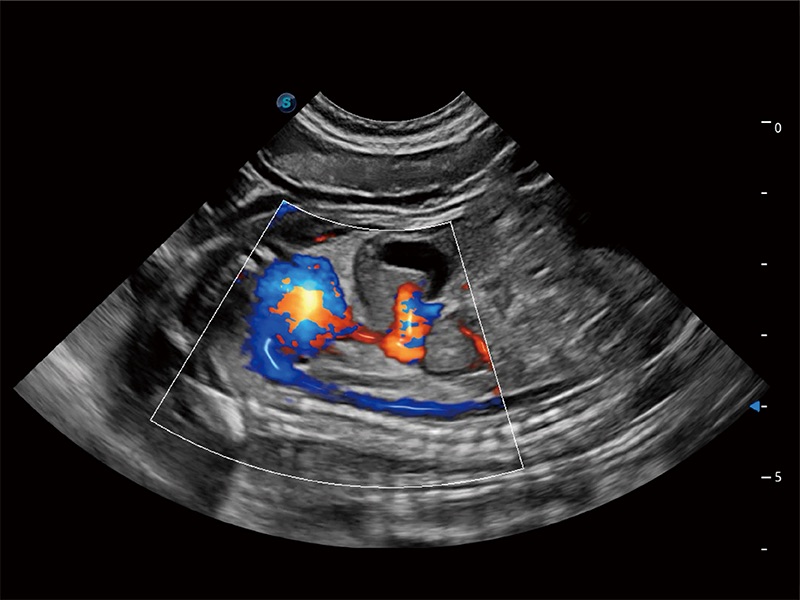

(犬)胎儿主动脉弓立体血流

• Bright Flow 立体血流成像

在传统二维血流成像的基础上,呈现血流的立体感,具有动感的生命力之美。即便是微小的血管也能轻松应对,提高了血流的视觉敏感性。